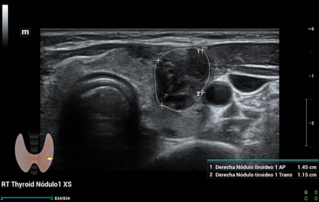

![multiparametric-ultrasound-thyroid-nodule.thumb.319.319 Ultrasound Journal 32 - Multiparametric Ultrasound for the Characterization of Thyroid Nodule: A Case Report]() Ultrasound Journal 32 - Multiparametric Ultrasound for the Characterization of Thyroid Nodule: A Case ReportExplore the case report on the use of multiparametric ultrasound, including CEUS and elastography, for the characterization of thyroid nodules using Mindray Resona I9, setting a new standard in non-invasive diagnostic techniques.Ultrasound Cases | General imaging | Ultrasound 2024-12-30

Ultrasound Journal 32 - Multiparametric Ultrasound for the Characterization of Thyroid Nodule: A Case ReportExplore the case report on the use of multiparametric ultrasound, including CEUS and elastography, for the characterization of thyroid nodules using Mindray Resona I9, setting a new standard in non-invasive diagnostic techniques.Ultrasound Cases | General imaging | Ultrasound 2024-12-30 -